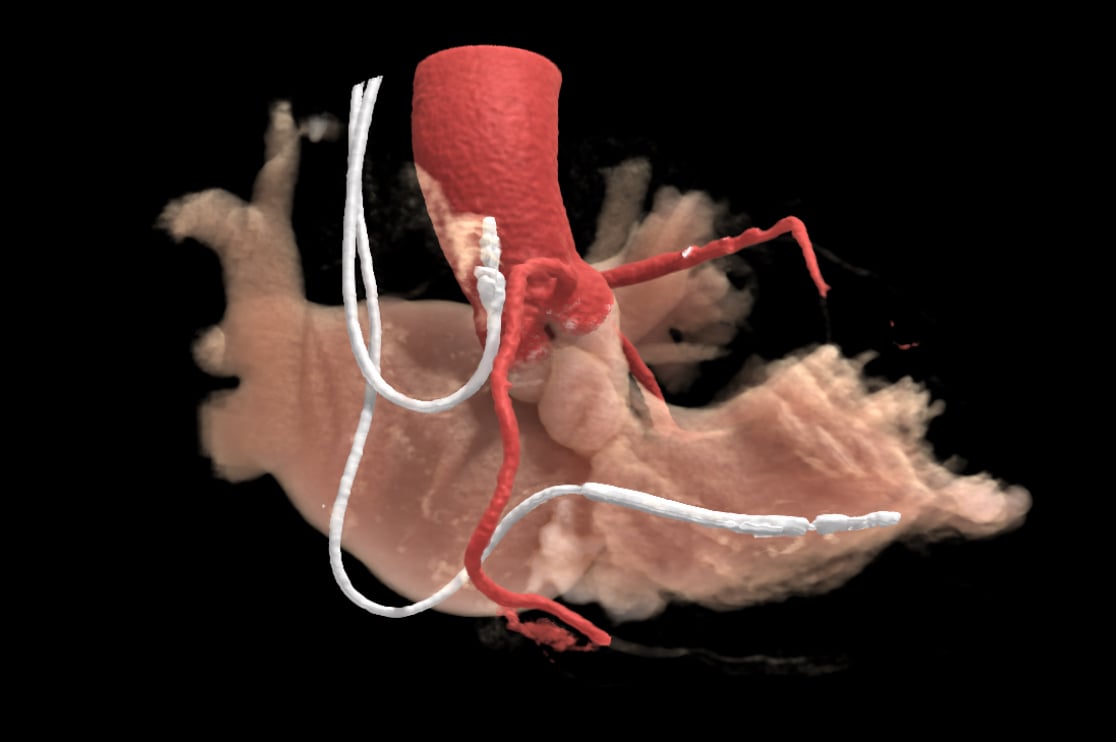

A cardiac CT of a patient with pacemaker leads, which can be challenging to get good images due to metal artifact. This image was rendered from using Canon's AiCE AI-assisted interactive reconstruction with Global Illumination 3-D rendering from a scan on an Aquilion One Genesis SP system.